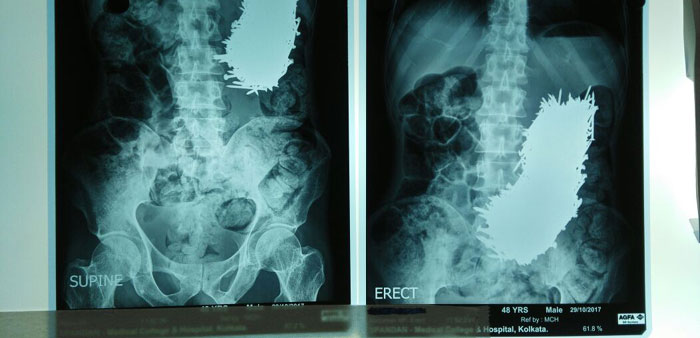

तर मंडळी, ‘कलकत्ता मेडिकल कॉलेज अँड हॉस्पिटल’ मध्ये एक माणूस आला. त्याच्या पोटाच्या वरच्या भागात दुखत असल्याची त्याची तक्रार होती. डॉक्टरांनी तपासणी केली, एक्स-रे काढला आणि मग त्यांना दिसलं की या माणसाच्या पोटात तर चक्क खिळे आहेत.

या माणसाने ऑक्टोबरच्या पहिल्या आठवड्यापासून जेवण सोडलं होतं. खरं तर खूप पूर्वी पासून तो खिळे खात होता पण हे प्रमाण हाताबाहेर गेल्यामुळे त्याच्या पोटात दुखू लागलं आणि त्याची रवानगी हॉस्पिटल मध्ये झाली.

सर्व खिळे बाहेर काढल्या नंतर त्यांची संख्या तब्बल ६३९ होती. प्रत्येक खिळा हा दोन ते अडीच इंच लांबीचा होता. तुम्ही फोटो मध्ये हे पाहू शकता.